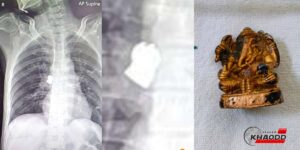

"พระพิฆเนศ" ปางประทานพร

พระพิฆเนศ” และต้องเป็นพระพิฆเนศปางประทานพร ให้พรโชคลาภสุขสมหวัง พรจะเป็นจริงได้คนที่ขอจะต้องมีใจที่เป็นบริสุทธิ์และเป็นคนดี